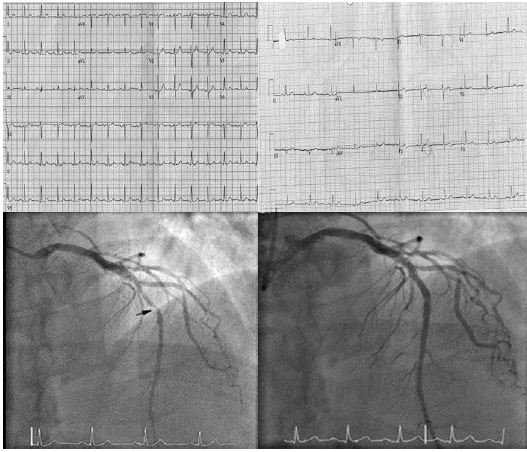

Paciente varón de 39 años con antecedentes familiares de cardiopatía isquémica (1 infarto de miocardio a los 35 años y un abuelo con muerte súbita a los 45 años), sin hábitos tóxicos.

Figura 1:ECG previo en ritmo sinusal, ECG a la llegada a urgencias con ondas T bifásicas en V2 y V3 característica del síndrome de Wellens de tipo A y coronariografía donde se observa lesión suboclusiva del 95% en el segmento medio de la descendente anterior así como normalización del ECG tras coronariografía.

Acude al servicio de urgencias por presentar un episodio de dolor torácico mientras jugaba al fútbol, descrito como sensación opresiva en el hemitórax izquierdo que duró aproximadamente 5 minutos, tuvo que detener el juego, sin otros síntomas relacionados. A la llegada del equipo de urgencias presentó un nuevo episodio de dolor torácico con características similares e irradiando al brazo derecho. Se administró aspirina y morfina IV. El ECG mostró una depresión del segmento ST (> 1 mm) en el punto J en las derivaciones precordiales en V2-V4 con ondas T hiperagudas. El paciente fue inmediatamente llevado al laboratorio de cateterismo con una lesión crítica del 95% de la DA, dos stents liberadores de fármacos fueron colocados.

Figura 2:ECG muestra que muestran patrón ST-T de Winter con depresión del segmento ST y T picudas en derivaciones precordiales, coronariografía que muestra lesión suboclusiva del 95% de la arteria descendente anterior así como ECG normalizada tras colocar stent de urgencias.